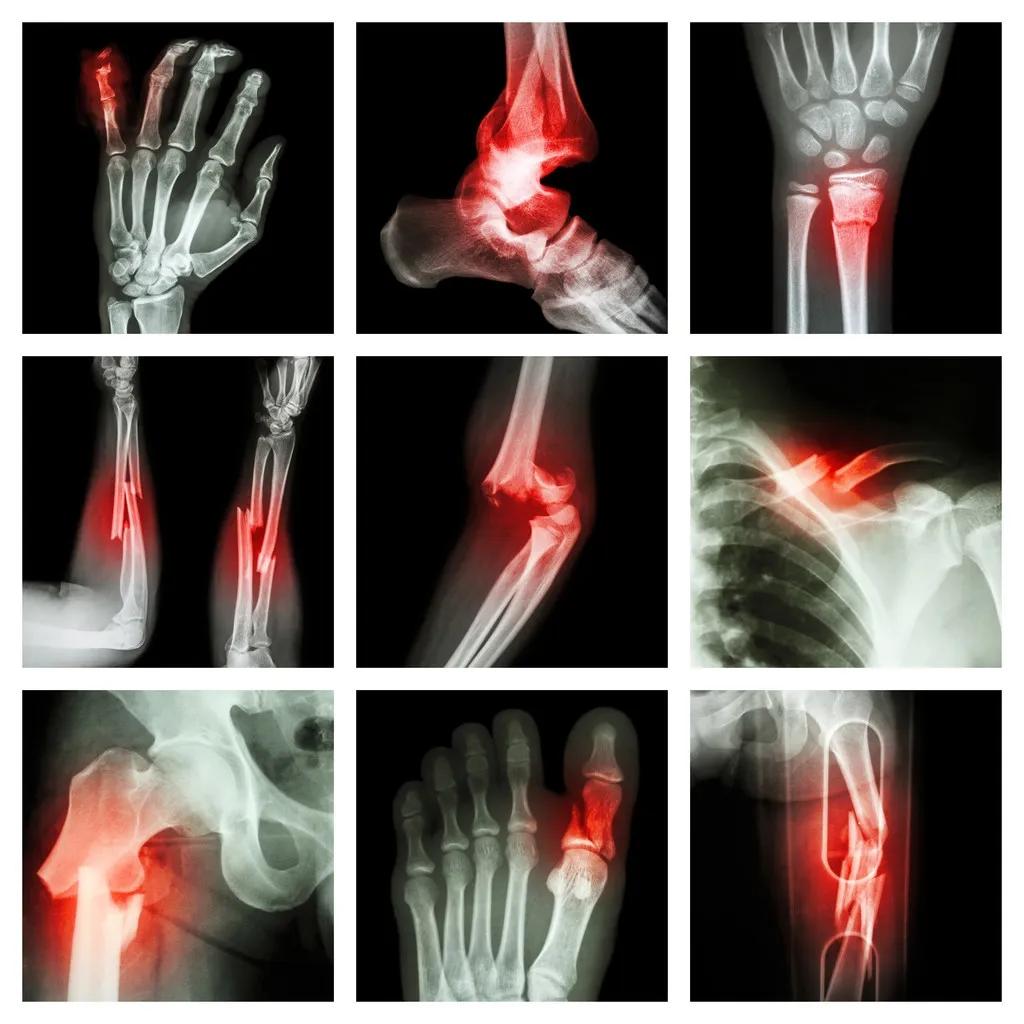

踝骨骨折后,正确的康复训练至关重要。它不仅能促进骨折愈合,还能帮助恢复关节功能,避免留下后遗症。然而,很多人对踝骨骨折后的康复训练并不了解,甚至存在一些误区。让我们一起来看看踝骨骨折后的康复训练应该如何进行。